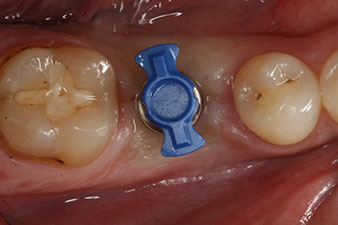

The implant was uncovered two months later and a gingiva former was screwed in (no picture).

After healing of the soft tissue, the implant stability was measured again before delivery of the prosthetic restoration.

Both values were virtually unchanged and were between the medium and the high range – where the lower value is always used as the reference value that determines the treatment.

Therefore, successful osseointegration and adequate biological stability could be recorded, which enabled an impression to be taken in the same session.